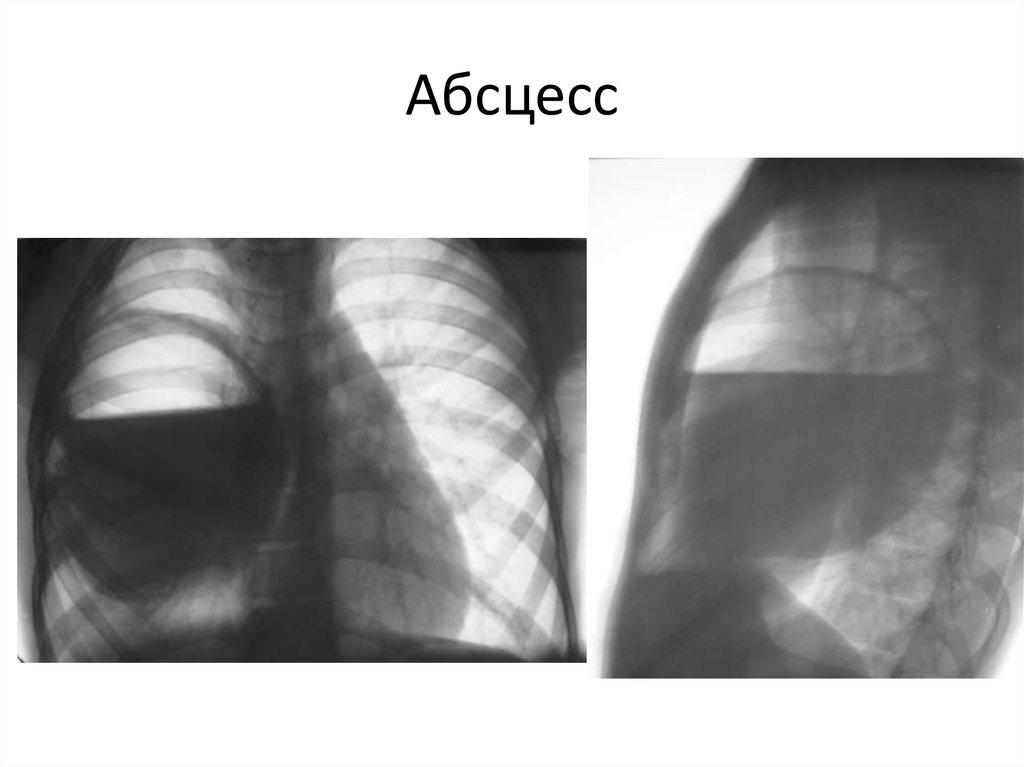

Абсцесс